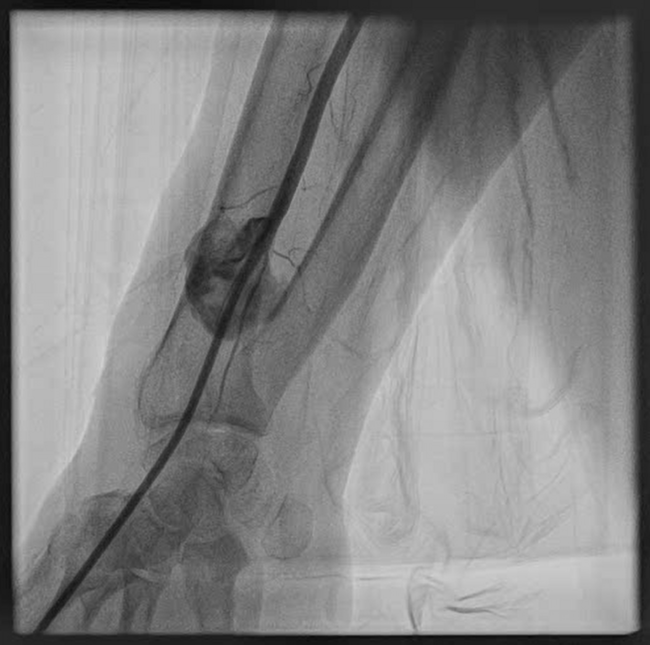

Endovascular Management of the Radial Artery: Success Through Minimal Invasion

Video Supplement to "Endovascular Management of the Radial Artery: Success Through Minimal Invasion."